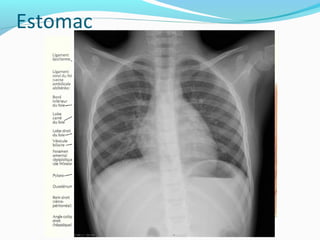

4/ L’estomac4/ L’estomac

Réservoir musculeux ou les aliments mastiqués vont

subir un brassage sous l’effet des contractions et du

suc gastrique

Situation: étage sus-mésocolique de

l’abdomen(épigastre et hypochondre gauche)

Configuration

externe :

2 portions:

-verticale (grosse

tubérosité+ corps)

-horizontale(antre et

pylore)

2 faces : ant et post

2 bords : grande et petite

courbure

2 orifices : cardia et

Estomac